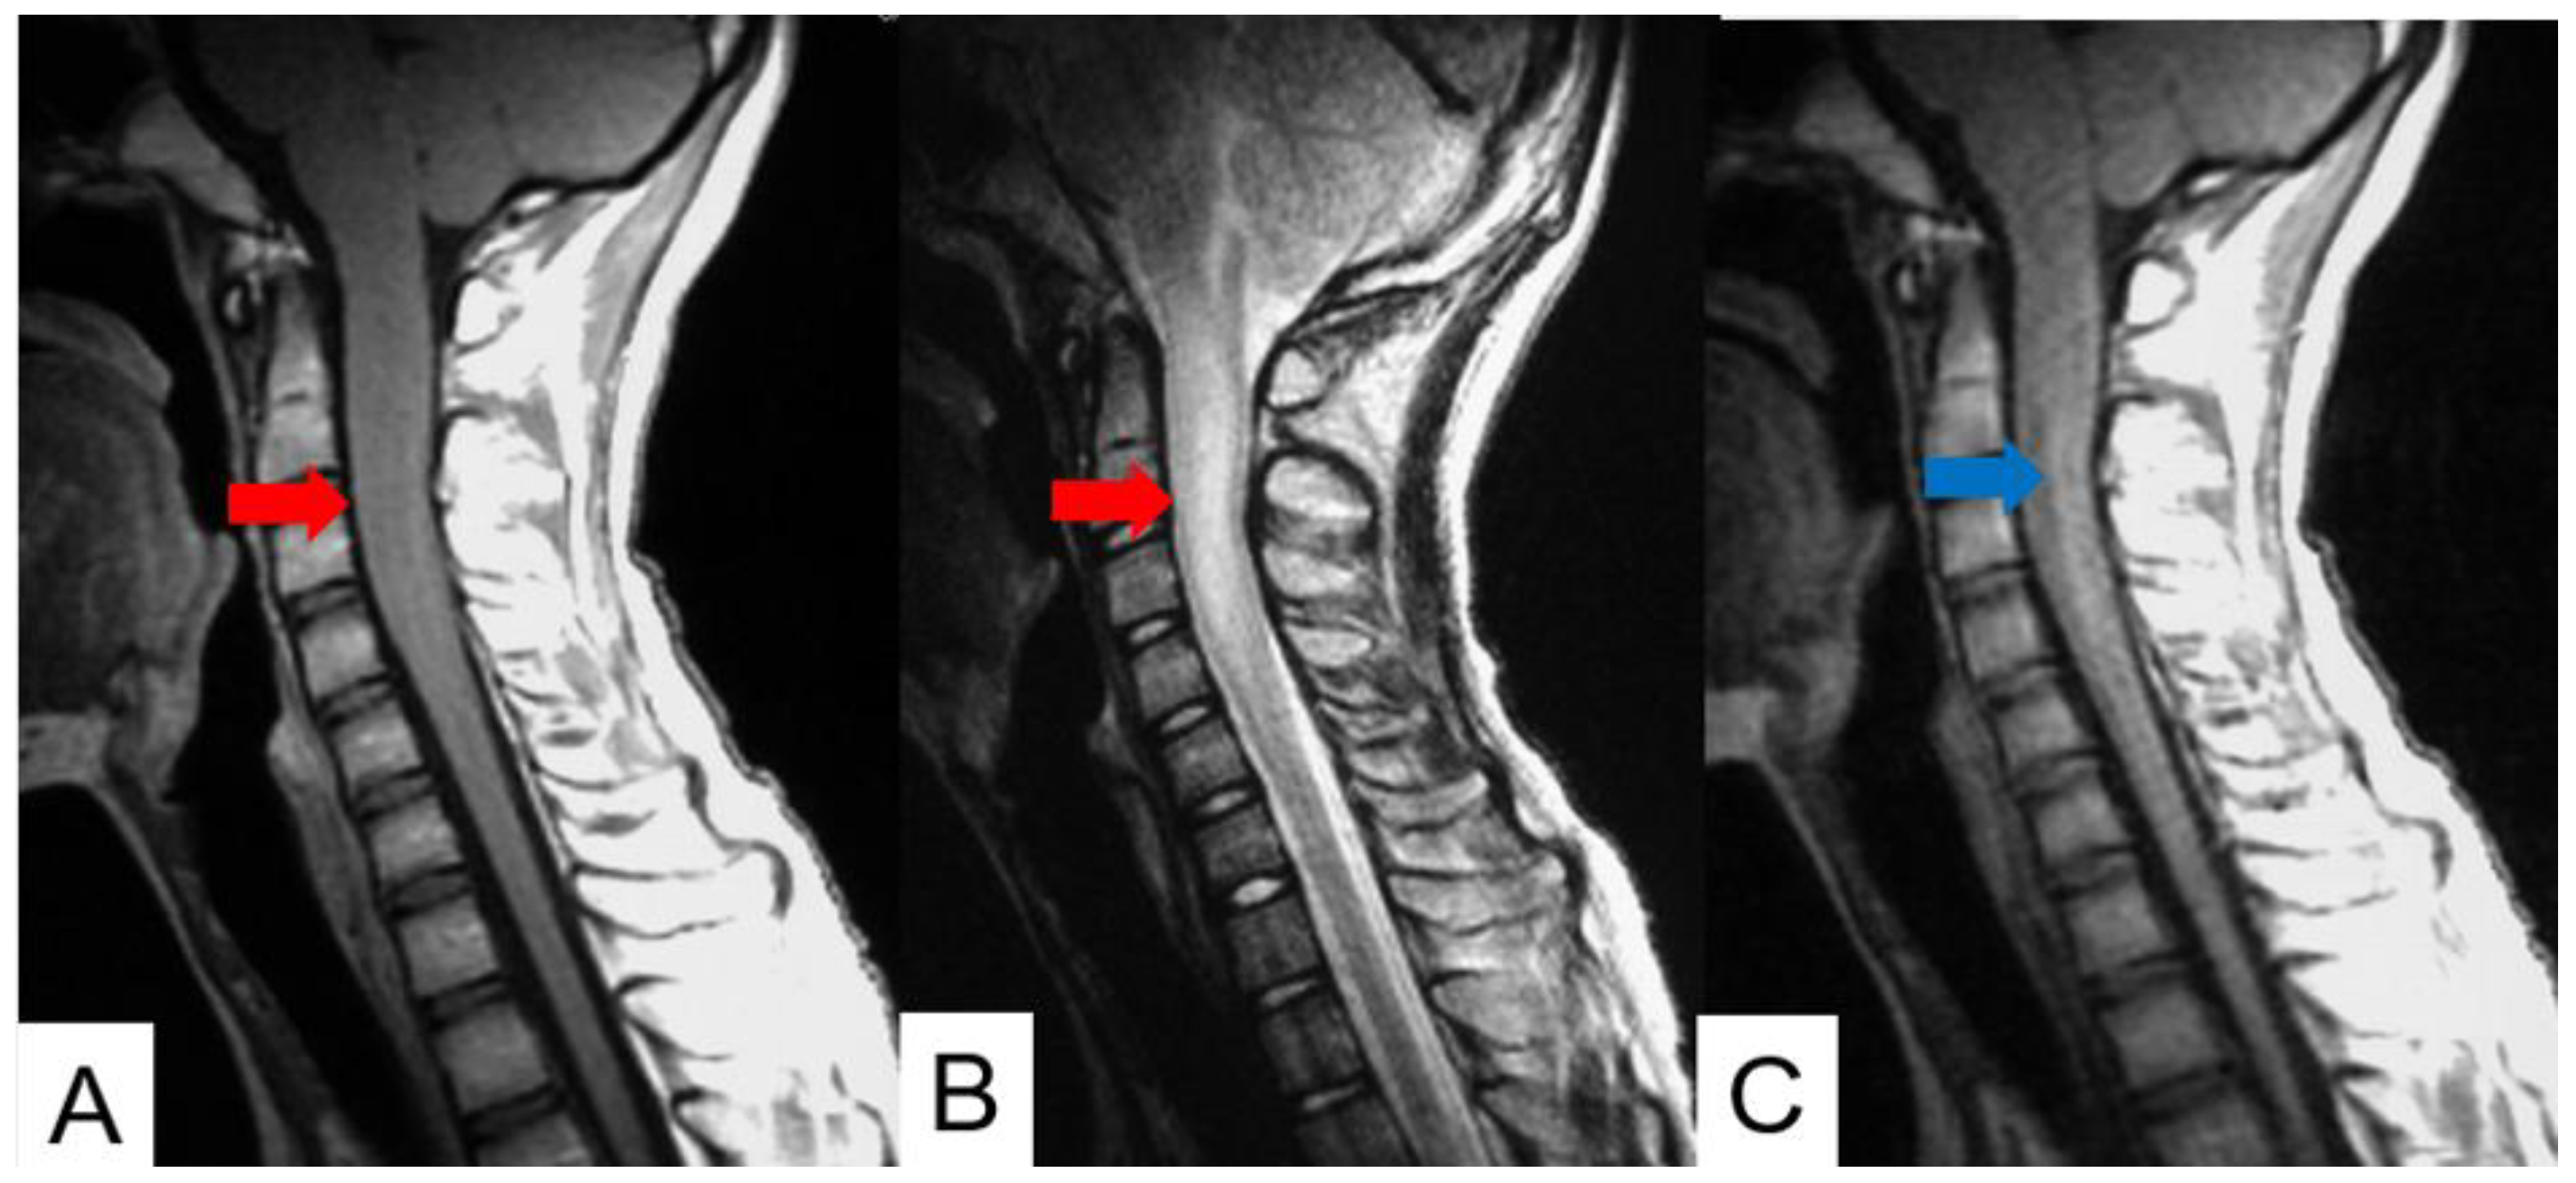

Schwannomas usually show low intensity in T1-weighted MR imaging and high intensity in T2-weighted MR imaging (Figure 1 and Figure 2). These tumors often enlarge alongside the nerve root and become a dumbbell-type [34]. The heterogenicity of a tumor indicates cystic change.

Figure 1.

Fifty-four M, spinal schwannoma. (A) T1-weighted midsagittal image, (B) T2-weighted midsagittal image, and (C) enhanced T1-weighted midsagittal image. Red arrows indicate tumor and blue arrow shows tumor enhancement. The tumor is mixed-intensity because of tumor necrosis.